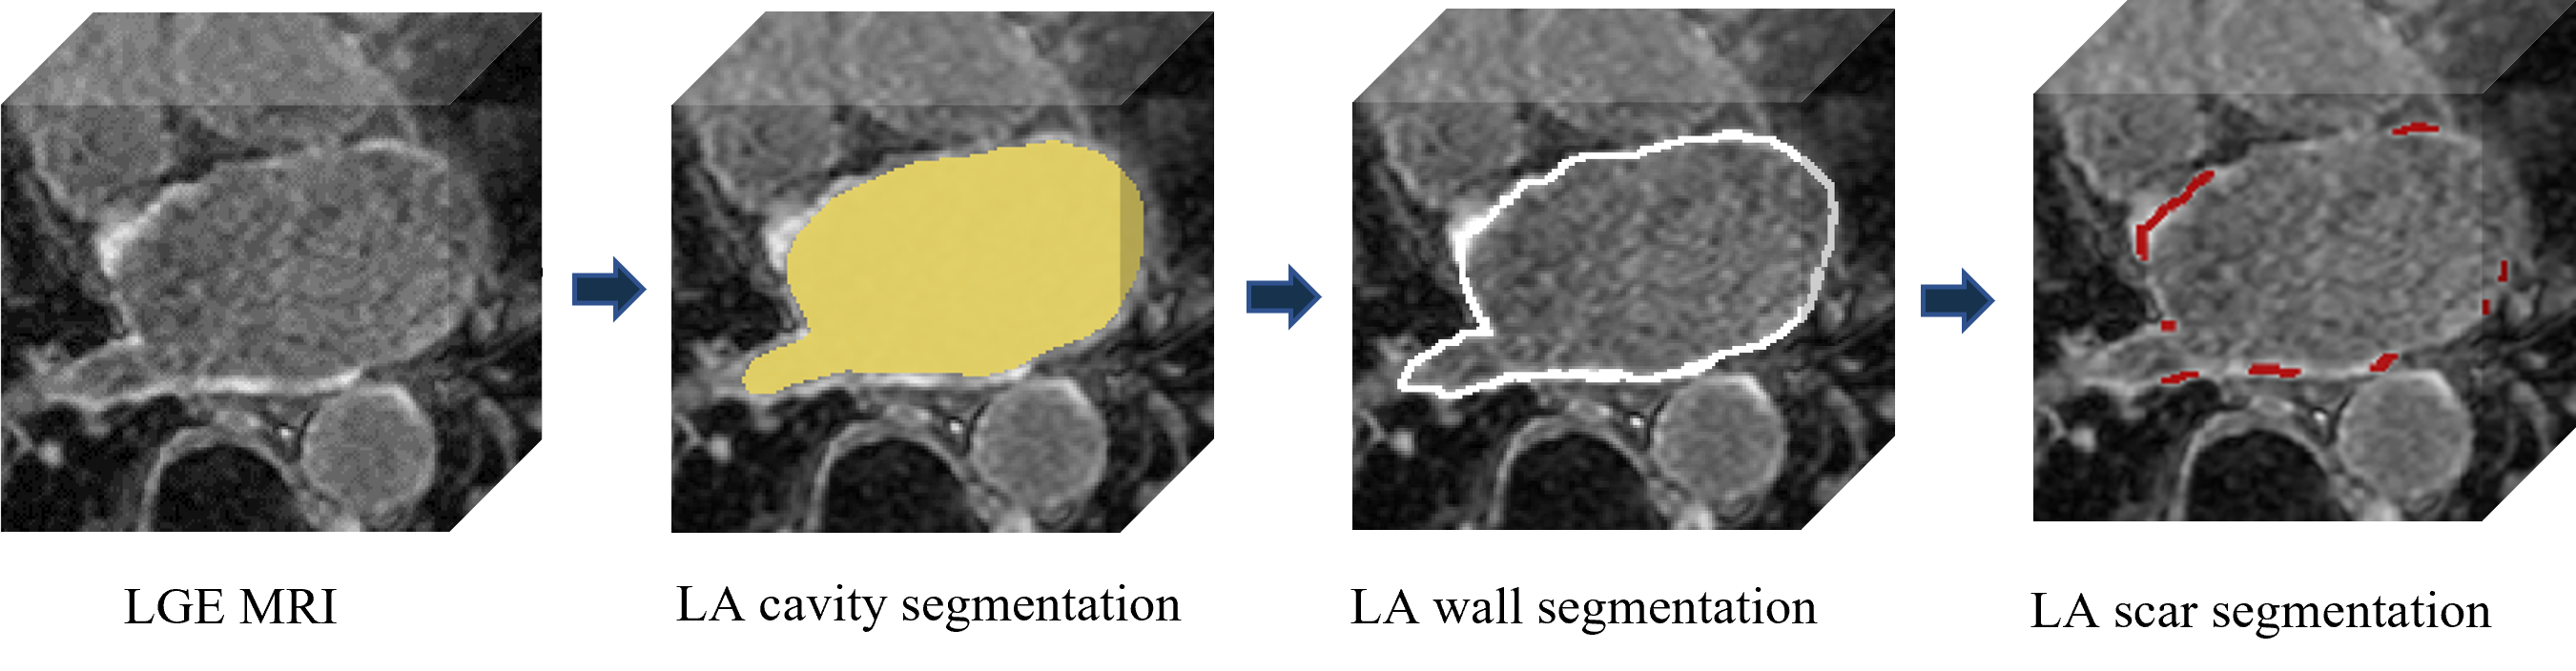

In terms of LA scar prediction, prior work predicts LA and LA scars separately without considering the relationship between them [16]. Meanwhile, the size of the scars is relatively insignificant, bringing difficulties in the prediction. Fortunately, LAs are much easier to be predicted, while LA scars are often detected near identified LA boundaries Fig. 2. Inspired by [29], we believe that combining the prediction of LAs and LA scars can be expected to improve scar segmentation performance.

In this paper, we propose a novel U-shaped GCN with Enhanced Transformer module (UGformer). It is a two-stage segmentation model by segmenting the LA before quantifying the irregularly shaped LA scars. It consists of a novel transformer block as the encoder, convolution blocks as the decoder, and skip-connections with a GCN as the bridge.

We first trained the LA segmentation on task 2. The obtained model was loaded as the pre-training model for task 1. In detail, in the initial stage, the segmentation model was trained with all the LA labels available, obtaining the LA prediction model (LAPM). Then, we used the LAPM to roughly segment the targetted LA region, according to which images in the training set were cropped to train the scar prediction model (SPM). Specifically, the cropping region of interest (ROI) was implemented via , while , , , were boundary pixels of the predicted LA region, was an empirically-selected tolerance of LA prediction. Finally, the prediction map was restored to its original size using zero padding.